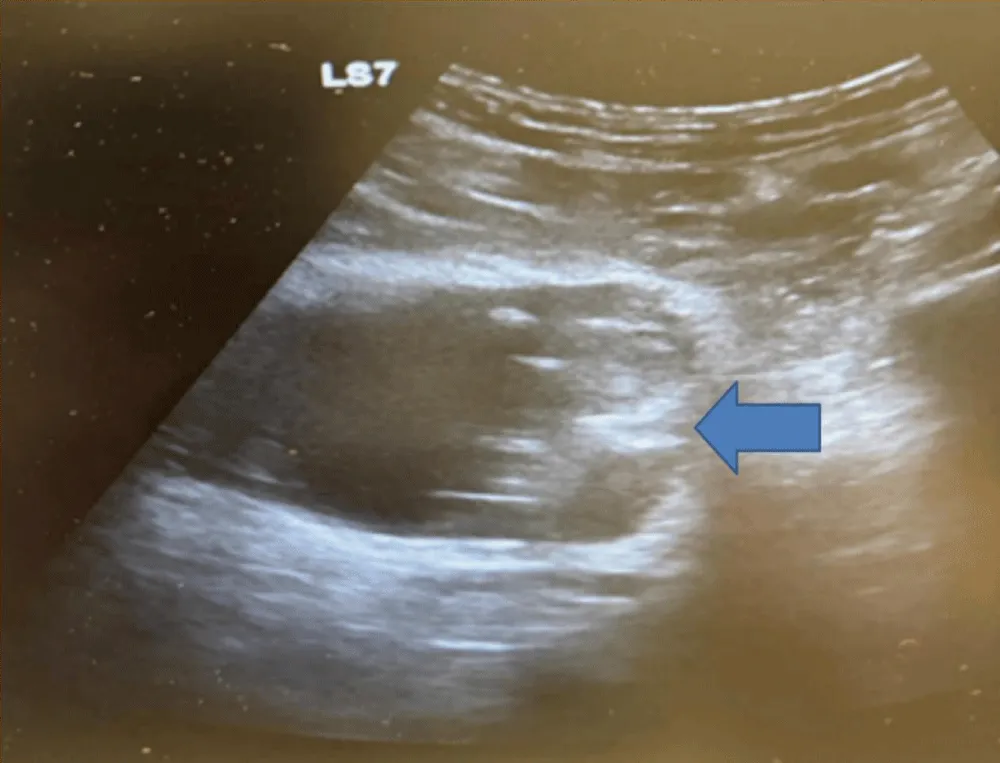

Abdominal ultrasound revealed a well-defined sessile, non-mobile, and mildly vascularized echogenic intravesical mass arising from the left lateral bladder wall (Figure 1).

Figure 1: Radiological Assessement. Abdominal ultrasound showing a well-defined sessile, non-mobile, and mildly vascularized echogenic intravesical mass arising from the left lateral bladder wall.